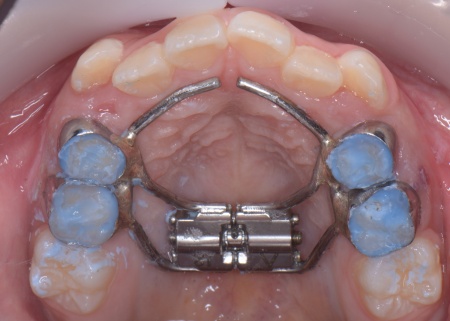

まず、上顎に顎の骨を広げるための固定式の矯正器具「急速拡大装置」を、下顎には歯並びの幅を広げるための「リンガルアーチ」を装着します。

治療を進めた結果、上顎は約6mm拡大し、歯が並ぶためのスペースを確保することができました。